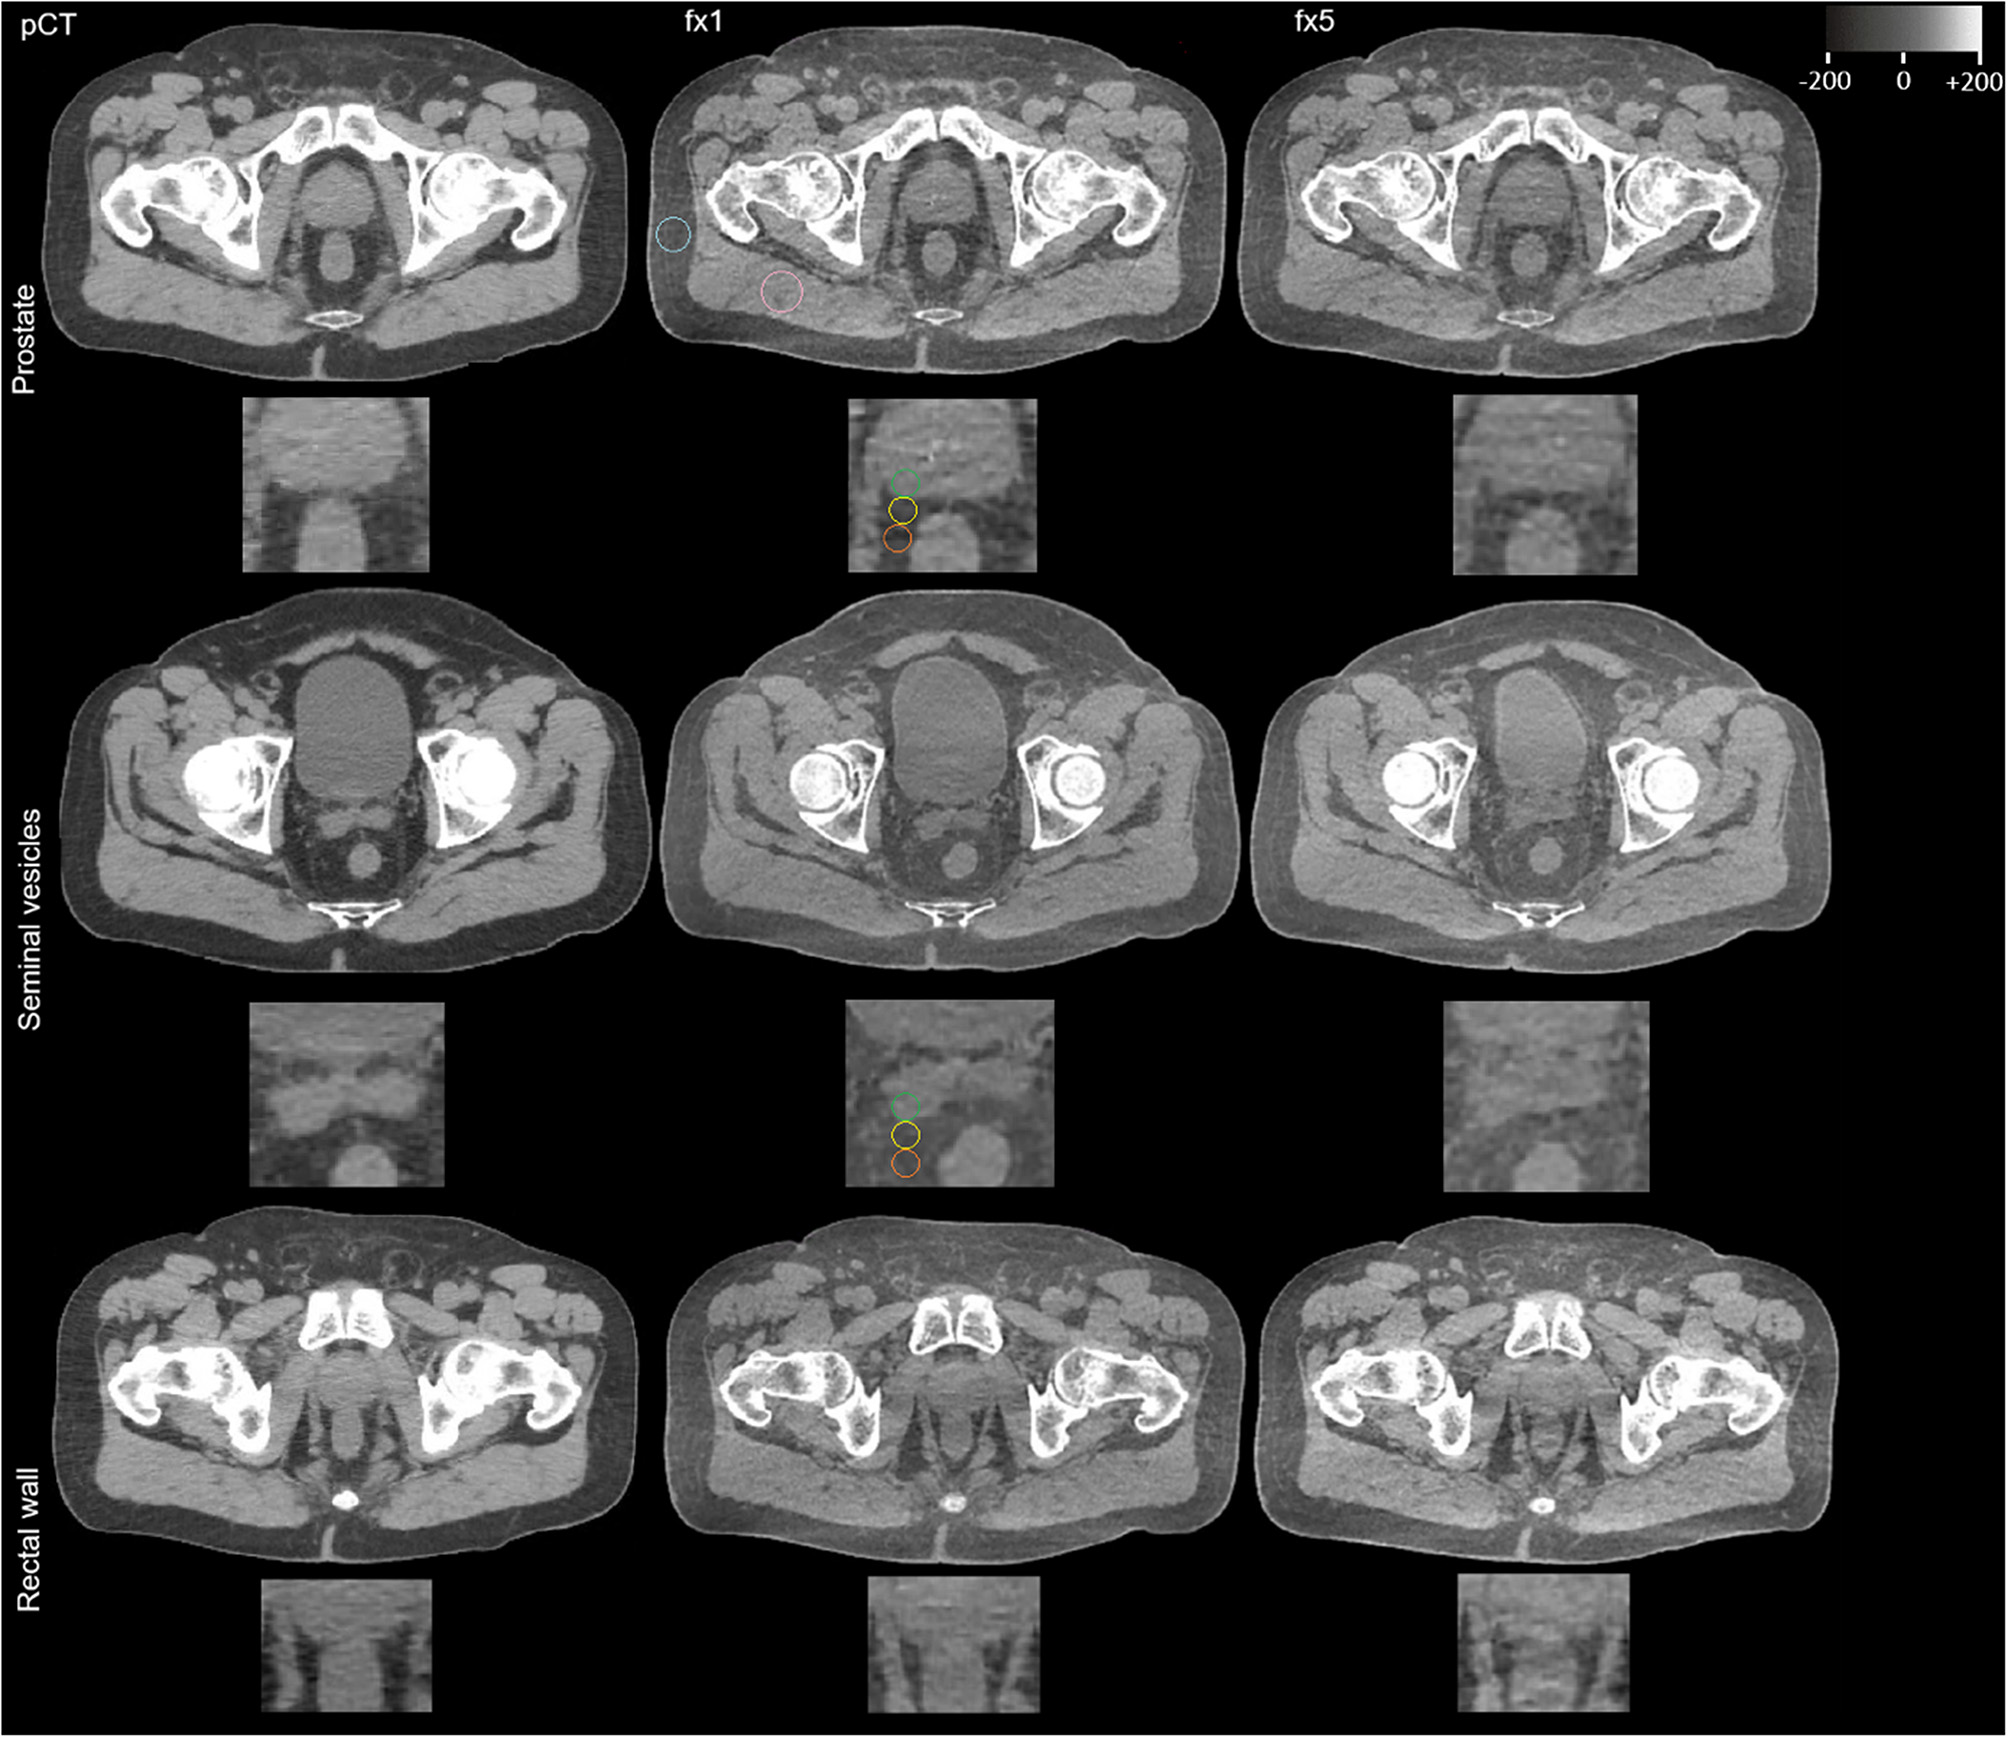

Advanced HyperSight™ imaging for patients with adaptive SBRT of prostate cancer: a longitudinal analysis of tissue demarcation.

Ralf Schmidt, Thanh Nguyen, Alicia S Bicu, Paula Cvachovec, Victor Siefert, Miriam Eckl, Marvin Willam, Matthias F Froelich, Stefan O Schoenberg, Michael Ehmann, Daniel Buergy, Sven Clausen, Jens Fleckenstein, Frank A Giordano, Judit Boda-Heggemann, Constantin Dreher